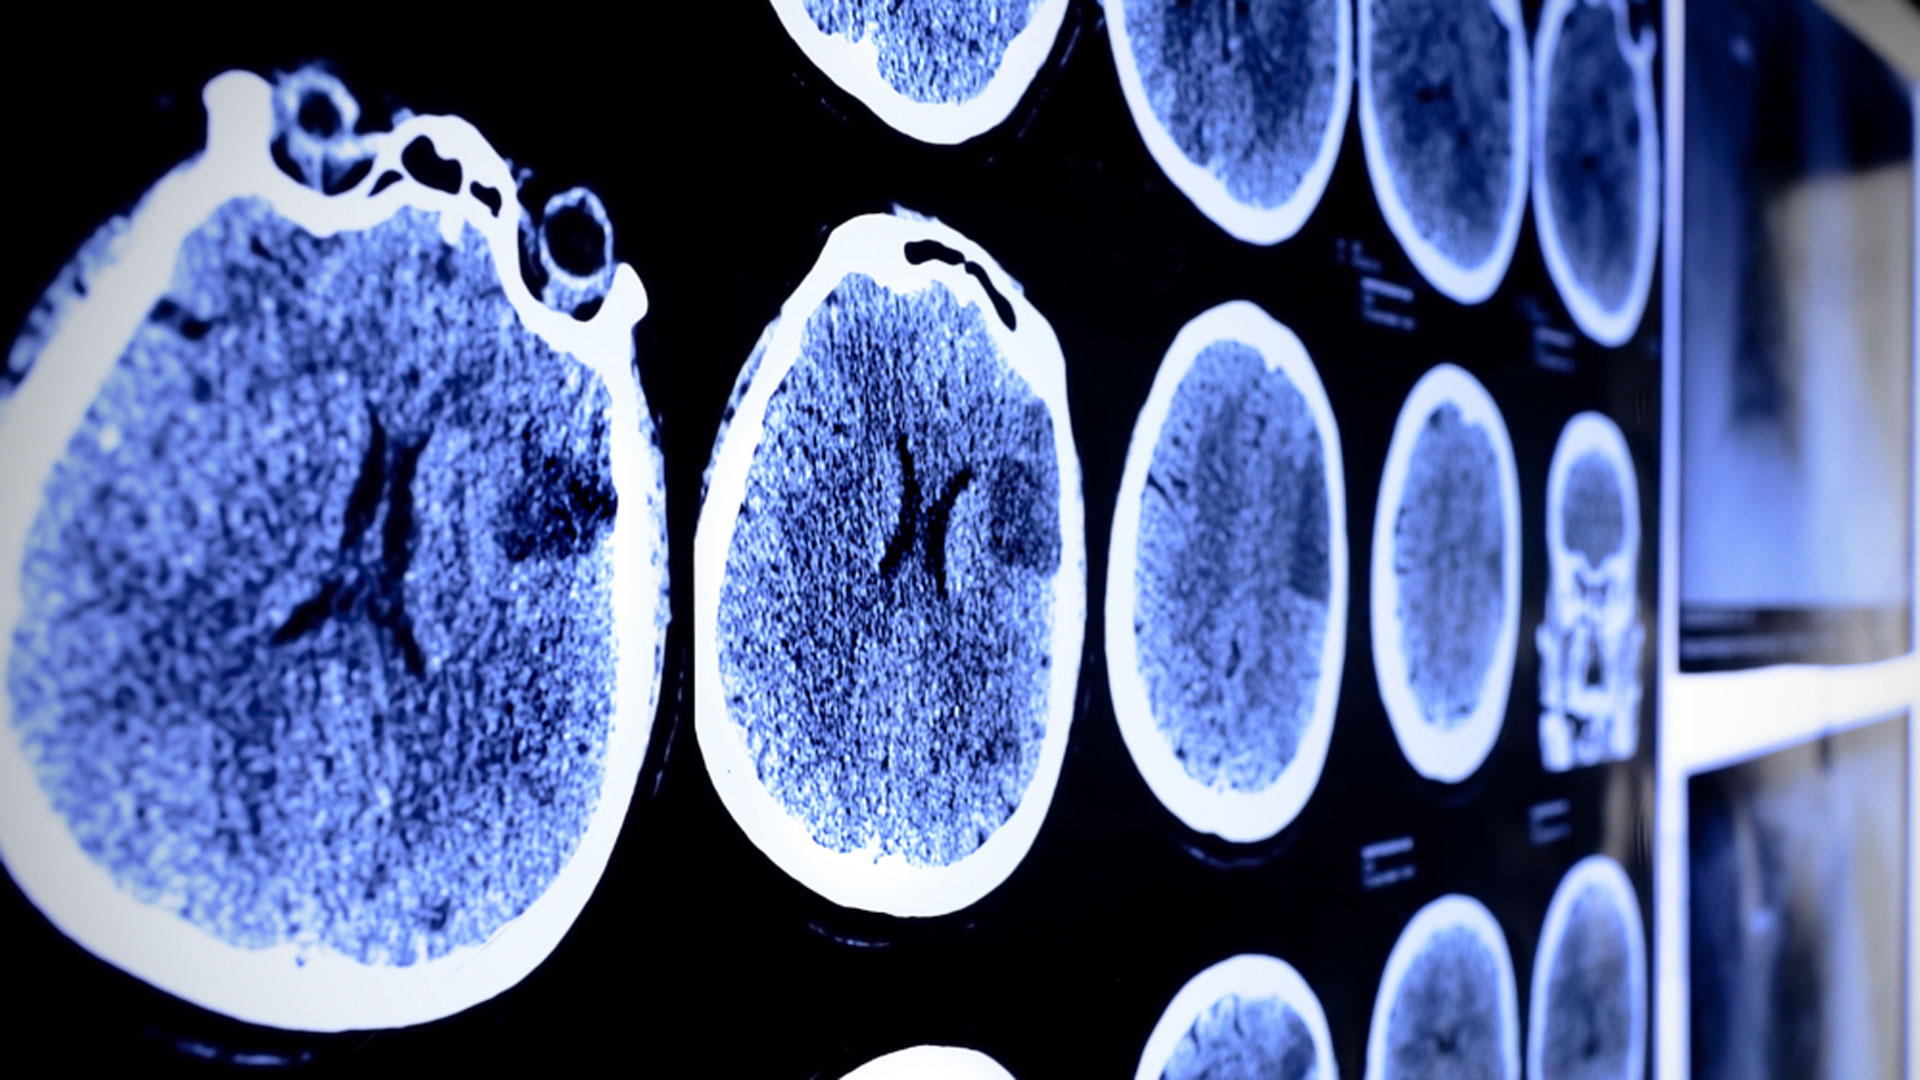

El paciente murió por una neumonía. Tras su fallecimiento, los investigadores pudieron examinar su cerebro con detenimiento. Aunque tenía muchos de los cambios comunes que se observan en Parkinson (como la pérdida de células cerebrales y el aumento de la inflamación en la sustancia negra, una región cerebral clave relacionada con el trastorno), faltaban algunos otros cambios típicos.

Los investigadores no pudieron encontrar cuerpos de Lewy con alfa-sinucleína en ninguna de las regiones que normalmente se ven afectadas en la enfermedad de Parkinson. Se creía que la acumulación de esos cuerpos de Lewy provoca la muerte celular en regiones cerebrales. Tras hacer el estudio sobre el paciente, ahora tienen otra perspectiva.

“Esto era inusual”, dijo la autora principal del estudio, Rika Yamashita. “Cuando miramos más allá, nos dimos cuenta de que el paciente tenía inclusiones que contenían otro tipo de proteína: la proteína llamada TDP-43″.

En Japón encontraron que el paciente que tenía síntomas de Parkinson tenía niveles alterados de la proteína llamada TDP-43/Archivo

En Japón encontraron que el paciente que tenía síntomas de Parkinson tenía niveles alterados de la proteína llamada TDP-43/ArchivoLa acumulación de la proteína TDP-43 se produce en otras enfermedades neurodegenerativas como la esclerosis lateral amiotrófica y la degeneración lobar frontotemporal, pero no suele asociarse al Parkinson. Sin embargo, este nuevo informe sugiere que su acumulación puede causar la pérdida de células en la sustancia negra, así como los síntomas motores típicos de la enfermedad de Parkinson.

“Este informe tiene implicancias en la forma de pensar sobre el desarrollo del trastorno de Parkinson”, explicó Goichi Beck, autor principal del informe. “Gran parte de la investigación actual que busca tratamientos para la enfermedad está muy centrada en la alfa-sinucleína, pero puede no ser la única proteína que causa la enfermedad. Nuestros hallazgos indican que la acumulación de TDP-43 puede ser una causa de la enfermedad separada de la acumulación de alfa-sinucleína”, señaló.